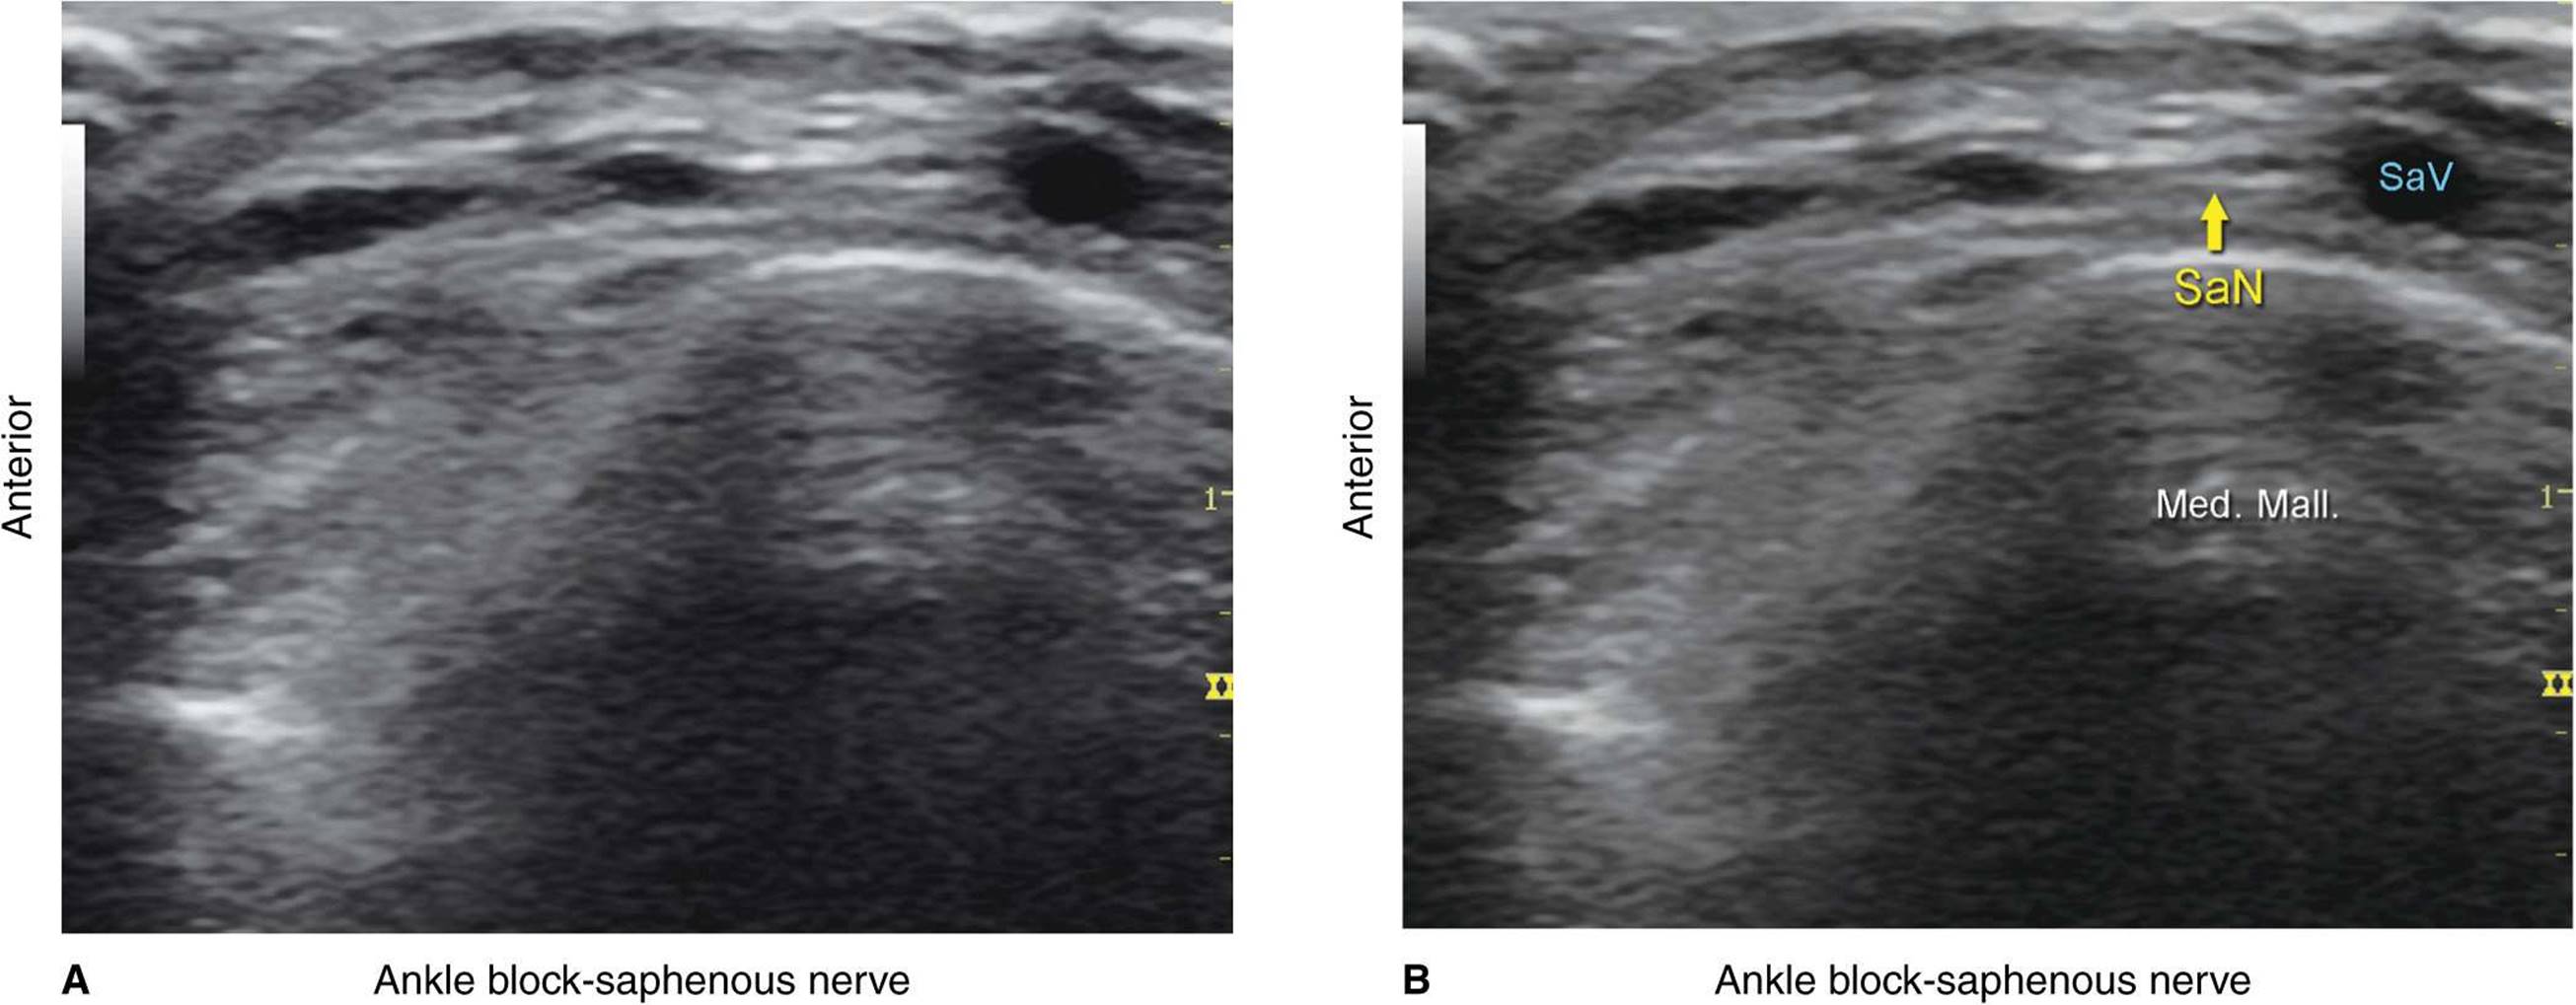

Saphenous Nerve

The saphenous nerve innervates the medial malleolus and a variable portion of the medial aspect of the leg below the knee. The nerve travels down the medial leg alongside the saphenous vein. Because it is a small nerve, it is best visualized 10–15 cm proximal to the medial malleolus, using the saphenous vein as a landmark (Figures 41-14, 41-15, and 41-16A, B). A proximal calf tourniquet can be used to assist in increasing the size of the vein. The nerve appears as a small hyperechoic structure.

FIGURE 41-15. Cross-sectional anatomy of the saphenous nerve (SaN) at the level of the ankle.

FIGURE 41-16. (A) Ultrasound anatomy of the saphenous nerve (SaN) at the level of the ankle. The SaN is seen just anterior to the small saphenous vein (SaV). (B) Ultrasound anatomy of the saphenous nerve with the structures labeled.